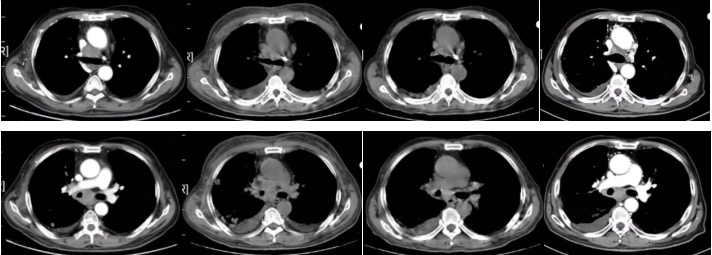

2022-03-31胸部平扫+增强CT:右肺中叶占位(2.6×4.7cm),考虑肺癌,双肺多发小结节(右肺中叶较大者长径约1.8cm),考虑转移。右侧锁区、纵隔及右肺门淋巴结增大(较大者短径约3.2cm),考虑转移。双肺间质性炎。左肺下叶钙化灶。右侧胸腔积液,心包积液。冠状动脉硬化斑块形成。

图1

图2